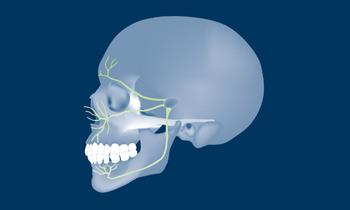

The understanding of the facial anatomy with its associated osseous and neurovascular structures is essential to the implant surgeon. During treatment planning and implant surgery, certain critical landmarks and boundaries must be respected. The anatomy of the maxilla and mandible is complex, and the implant surgeon should also keep in mind that many variations exist between individuals. The aim of this module is to review the basic anatomy of the facial region and to provide an overview of the important structures involved in implant dentistry in the average adult patient.

- describe the osseous structures of the maxilla

- describe the osseous structures of the mandible

- list the vascular structures of the maxilla and mandible

- list the neural structures of the maxilla and mandible